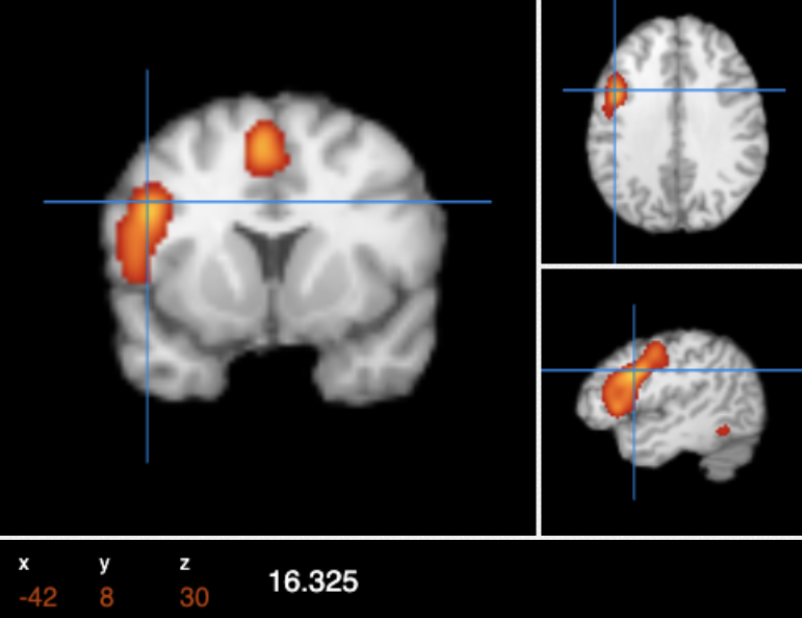

Cerebral Magnetics was developed based in part on the meta-analyses conducted from BrainMap. The BrainMap database allows free access to copyrighted data from imaging studies of 250,000 individuals. The image on the left is an example of a meta-analysis, in this case the analysis displays brain areas involved in speech.

All brains differ slightly in size and shape. Magnetic Resonance Imaging (MRI) allows clinicians to determine the exact location, per patient, of brain areas implicated in PTSD or MDR, for precise aiming of TMS.